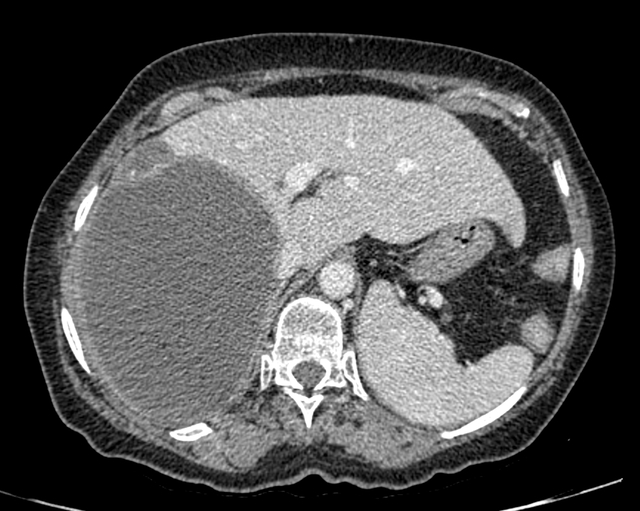

Hydatid Cyst: Image 2

CT of the abdomen/pelvis shows a circumscribed multilocular cystic lesion containing multiple smaller cysts in the right hepatic lobe associated with bulging of the capsule.